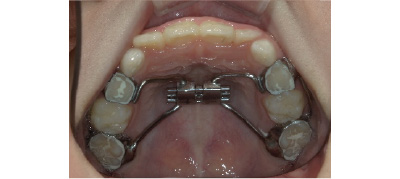

痛みの感じ方には個人差がありますが、多少はあると思っていただいた方が良いかと思います。小学生頃に行う第1期治療は、上下のアゴを広げて永久歯のスペースを作ります。こちらの装置は、痛みよりは食べにくい・喋りにくいなどの違和感の方がある方が多いです。

奥歯には金属のバンドが入りますので、噛んだ時に多少違和感や痛みを感じる方もいます。しかし、1週間ほど様子みていたけると徐々に慣れていきます。

通院頻度:顎を拡大したり前方へ動かしたりしている期間は2~4か月毎の通院が必要です。歯の表面にワイヤーを付けて歯を動かしている期間は1ヶ月毎の通院が必要です。